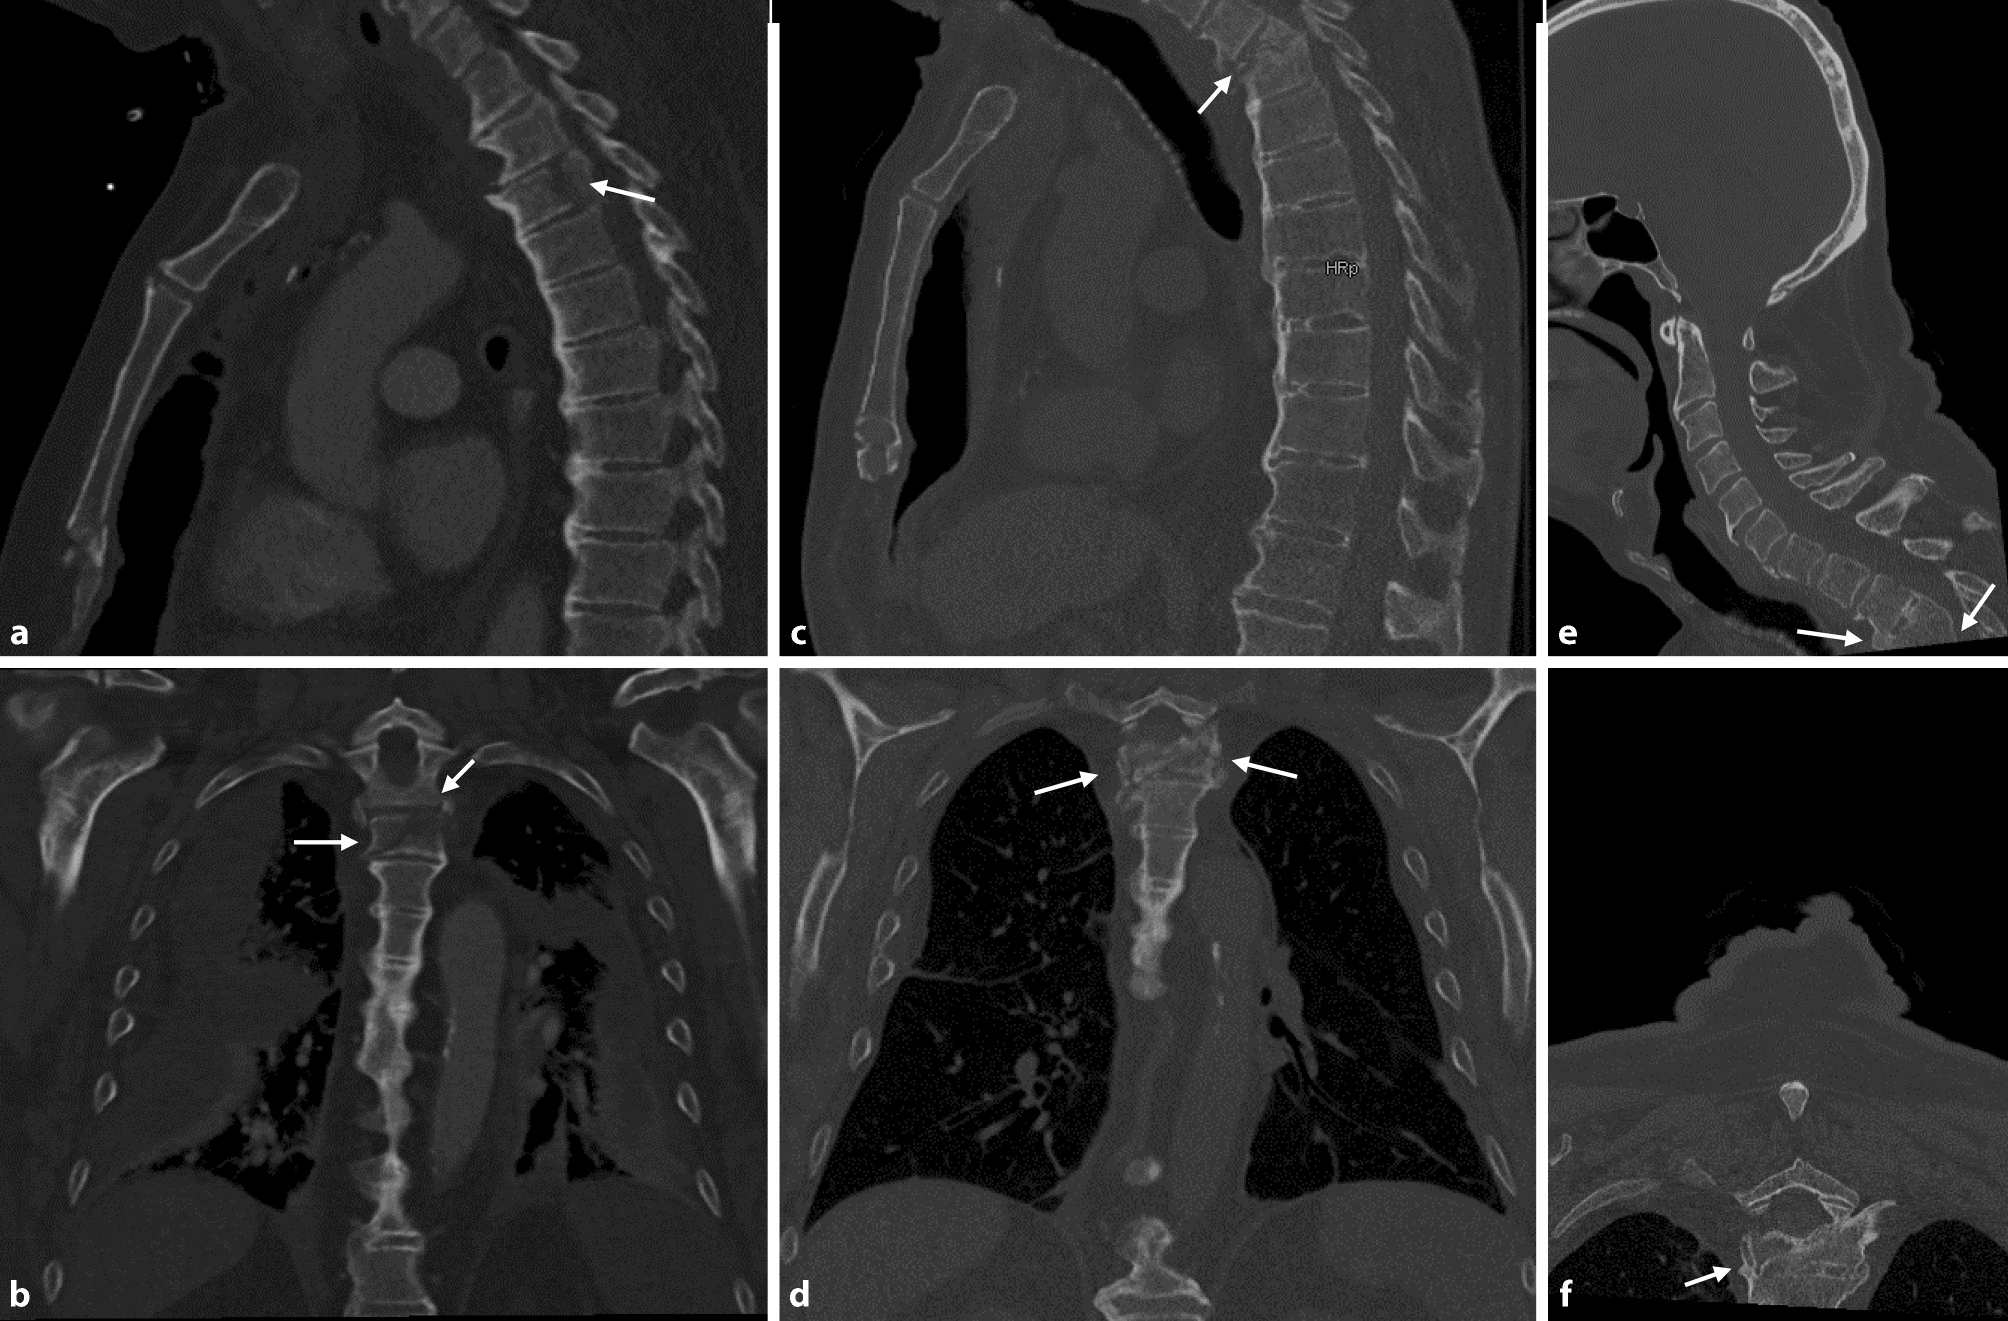

Fig. 1

a At initial trauma the chest X-ray (frontal plane) taken in a lying position only showed the fracture of the 5th right rib. b Areas of encapsulated air and mediastinal widening were visible 5 days later on the chest X‑ray in standing position (frontal plane). Subsequent CT scan in sagittal (c), axial (d), and frontal (e) plane showed an incomplete burst fracture (c,d,e), esophageal perforation (d), mediastinitis with fistula (d), left-sided pleural empyema (d), and entrapped air within the spinal canal (c). Endoscopy prior to emergency esophagectomy revealed extensive necrosis involving two thirds of the esophageal wall (f; necrosis visible to the right of the dashed line)

Diagnostic X‑rays of the thorax, cervical column and dens axis were taken, with novel hypodensities visible in left upper hemithorax and paramediastinum (Fig. 1b). Laboratory tests revealed leukocytes 7.3 G/L, hemoglobin 13.2 g/dL, creatinine 3.62 mg/dL, estimated glomerular filtration rate (eGFR) 15.58 ml/min, lactate dehydrogenase (LDH) 314 U/L and C-reactive protein (CRP) 484.2 mg/L. As pneumonia was suspected, a thoracic CT scan was performed and in addition to a lateral shaft fracture of the 5th right rib, another fracture of the 5th right rib at the costotransverse joint, a split fracture (AO spine type A2) of the 3rd thoracic vertebra (Fig. 1c, d, e), and signs of DISH, were diagnosed. Most strikingly though, a posttraumatic esophageal rupture at the level of the 3rd thoracic vertebra was diagnosed (Fig. 1d), with concurrent fistula between the mediastinum and pleural cavity (Fig. 1d), loculated left-sided pleural empyema, and entrapped air within the spinal canal (Fig. 1c). Notably, due to the patient’s serious general condition, a magnetic resonance imaging (MRI) scan to rule out injury of intervertebral discs, posterior structures, or the presence of accompanying spondylitis, was not carried out.

Blood cultures were obtained prior to the start of empirical i.v. antibiotic therapy with teicoplanin (1 × 1.2 g), clindamycin (3 × 600 mg) and piperacillin/tazobactam (3 × 4.5 g). Subsequent endoscopy showed widespread necrosis of the esophageal mucosa (Fig. 1f). The patient underwent emergency thoracotomy, revealing necrotizing mediastinitis, mediastinal abscess and loculated empyema due to a large defect in the esophagus and necrosis of two thirds of its wall caused by perforation due to a small vertebral fragment. Thus, the esophagus could not be preserved and emergency esophagectomy as well as mediastinal and pleural debridement were performed. Reconstruction by retrosternal gastric pull-up with cervical esophagogastrostomy had to be postponed for 3 days owing to the patient’s critical condition with sepsis, renal failure requiring hemodialysis and cardiorespiratory instability.